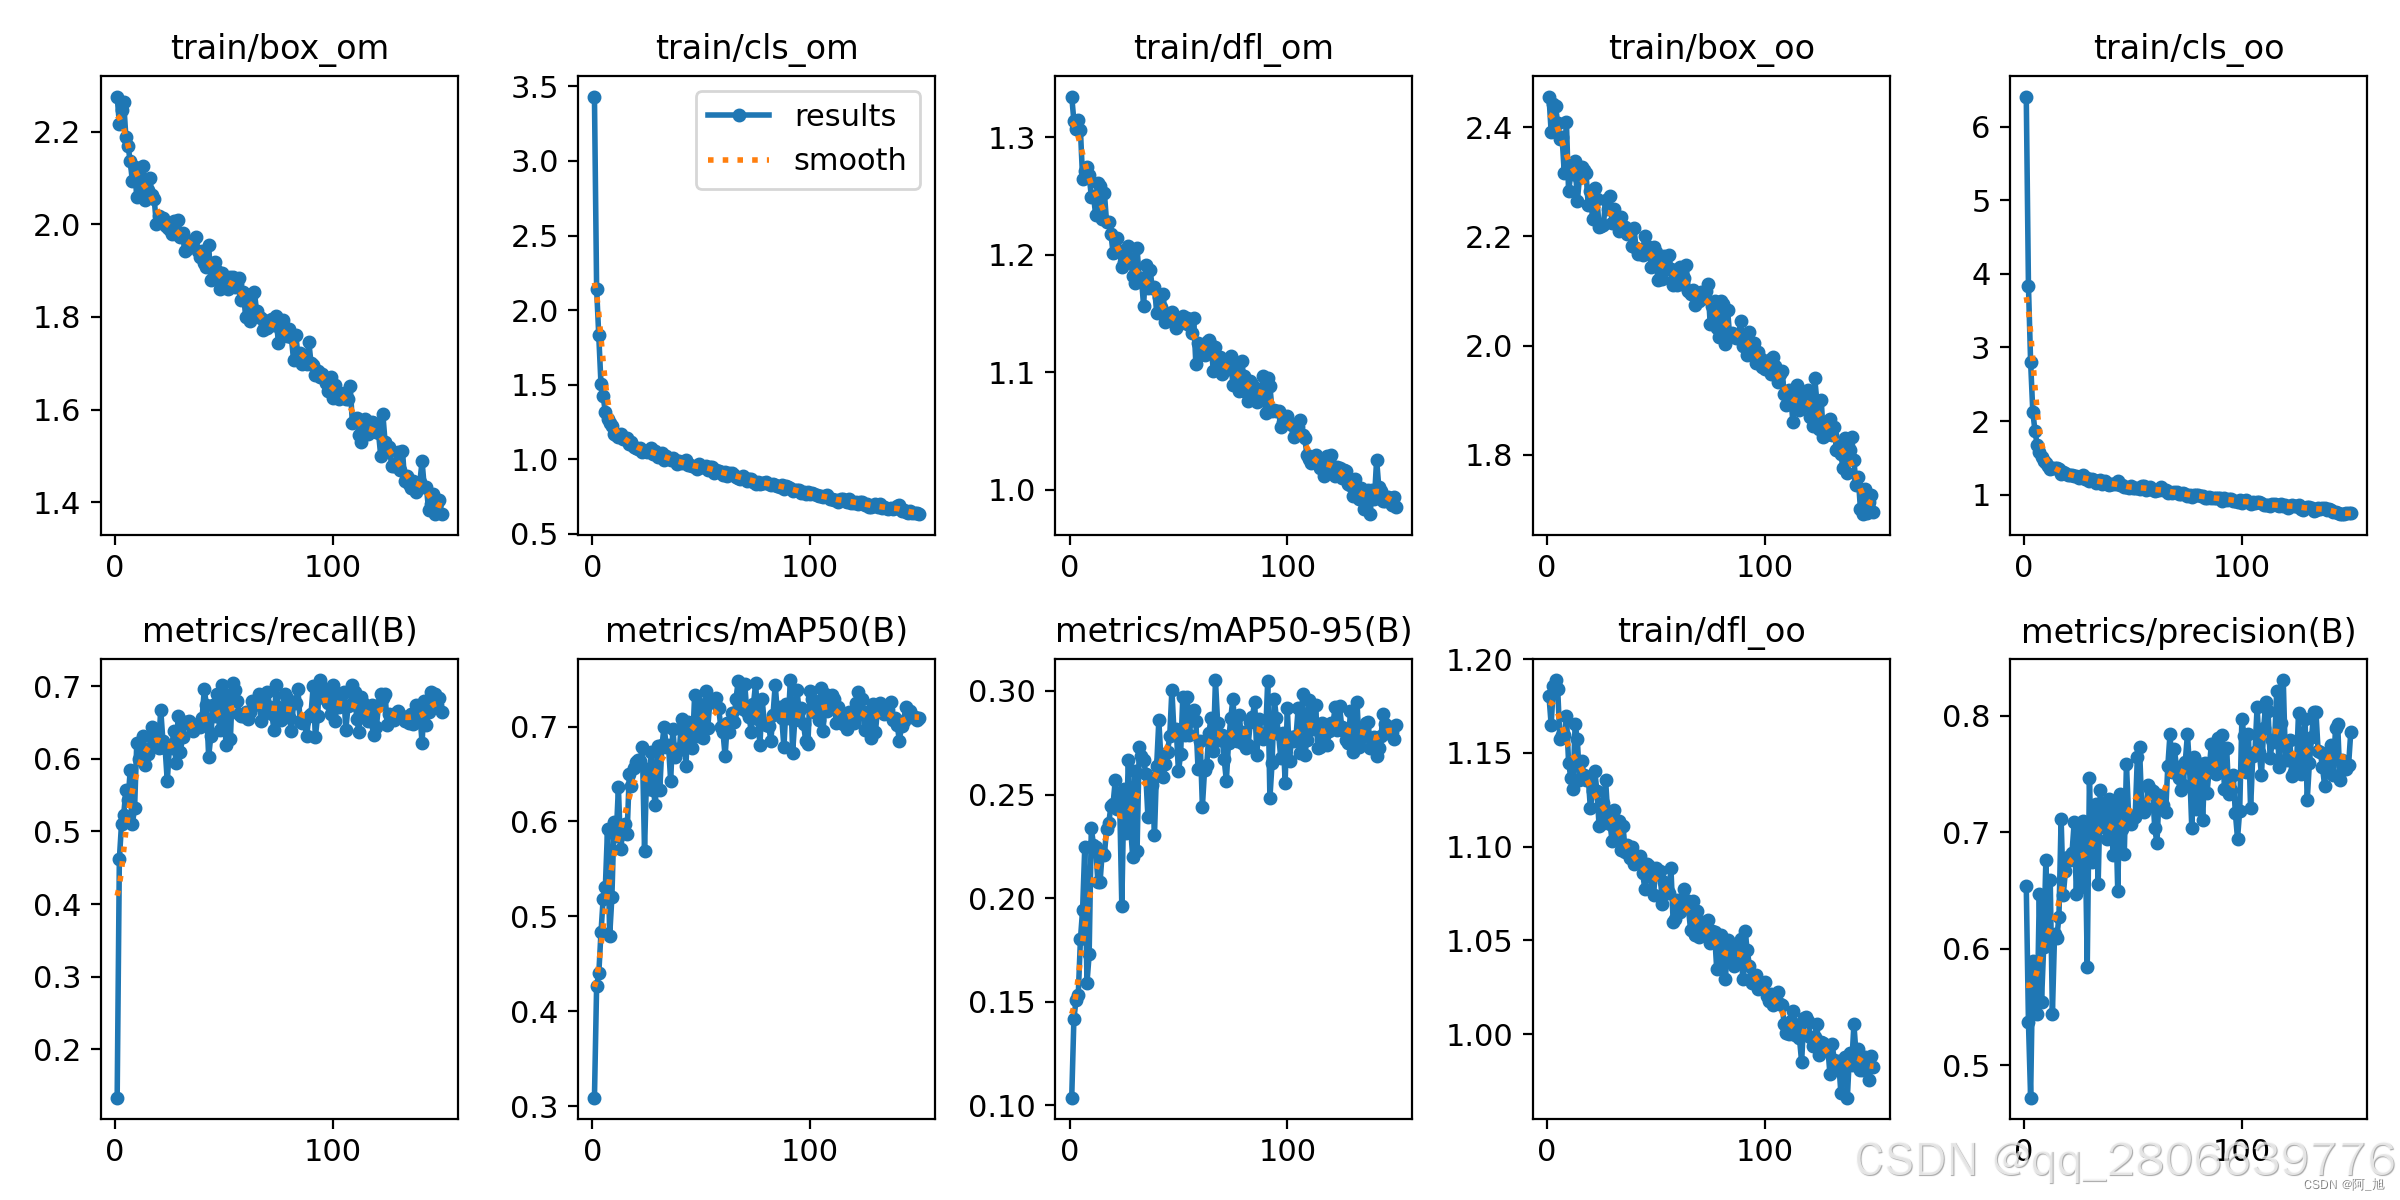

CT扫描图像的肾结石智能检测系统在医疗诊断方面提供了一种快速、准确的辅助工具,显著提高了医生识别和评估肾结石的效率。本文基于YOLOv10深度学习框架,通过1300张CT扫描的肾结石相关图片,训练了一个进行肾结石目标检测的模型,可以对CT扫描图像中的肾结石进行实时检测。并基于此模型开发了一款带UI界面的肾结石智能检测系统,更便于进行功能的展示。该系统是基于python与PyQT5开发的,支持图片、视频以及摄像头进行目标检测,并保存检测结果。本文提供了完整的Python代码和使用教程,给感兴趣的小伙伴参考学习,完整的代码资源文件获取方式见文末。